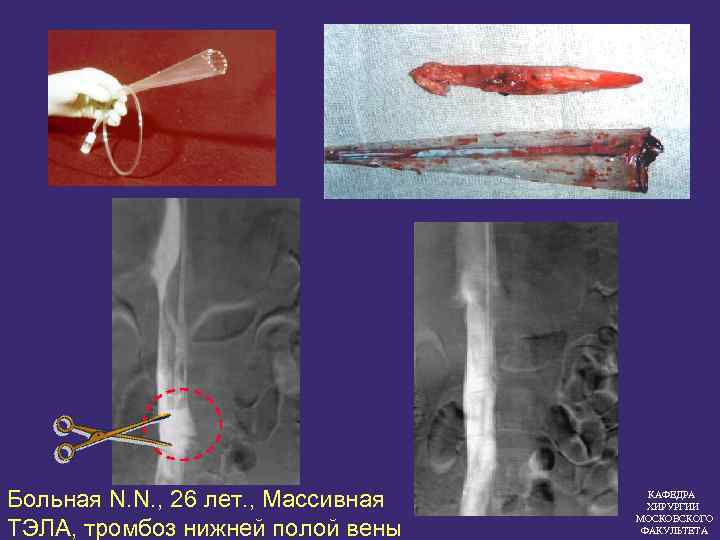

Больная N. N. , 26 лет. , Массивная ТЭЛА, тромбоз нижней полой вены КАФЕДРА ХИРУРГИИ МОСКОВСКОГО ФАКУЛЬТЕТА